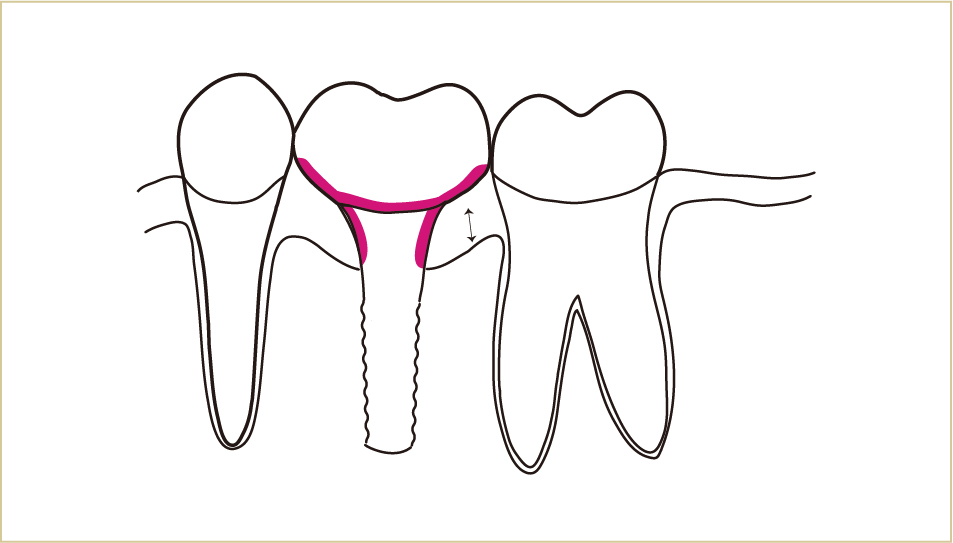

したがって、インプラントの周囲では、歯と歯肉の境目、特に歯肉の中へ歯ブラシの毛先を入れる感覚がより大切になります。

色の部分が汚れないようなイメージを持つことが重要。

歯周病の予防や治療でブラッシングするのと、ほぼ同じイメージで歯ブラシを当てていくことが大切。